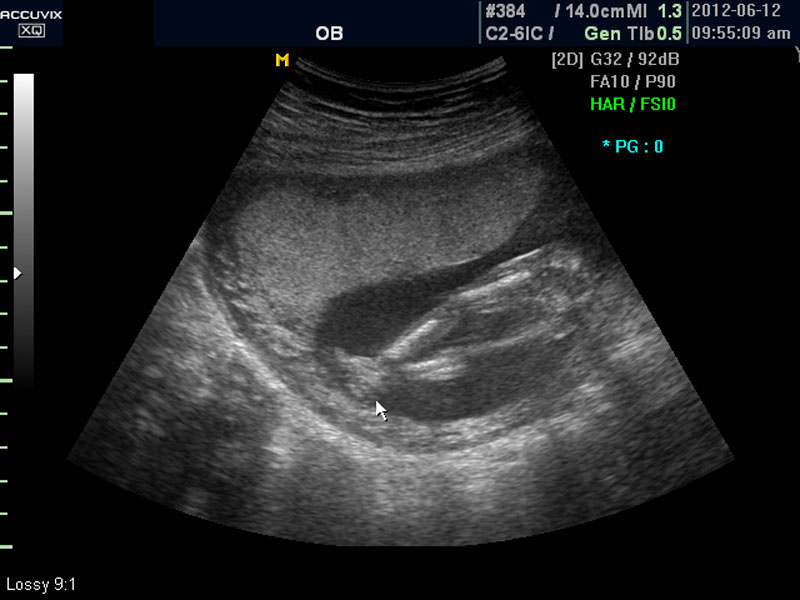

화면에서는 위쪽에 하얗게 균일하게 보이는 것이 태반의 모습입니다.

태반은 실제로 보면 피자처럼 둥그런 원판 모양이며 임신 후기로 갈수록 태아와 마찬가지로 크기가 커지고 두꺼워집니다.

양수의 양은 태아의 건강과 관련된 지표로 너무 많거나 너무 적으면 좋지 않은데 그 절대양을 측정할 수는 없어서 양수가 많은 부분의 깊이를 측정하거나 혹은 개략적으로 전체에서 차지하는 부분을 봐서 이상 여부를 판단합니다.

사진에서 검게 보이는 것이 양수입니다. 양수에 대하여는 색깔이나 밀도 등 다른 요소는 알기 어려워서 그 양만 가지고 판단을 하게 됩니다.

임신 초기나 중기의 양수 이상 중에는  대체로 태아의 건강 이상으로 인한 양소 과소증이 더 많은 편입니다.